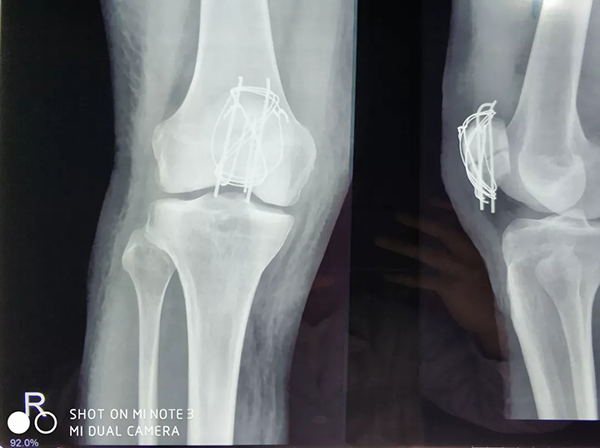

近日,廣安醫(yī)院關(guān)節(jié)科羅軍主任帶領(lǐng)科室團(tuán)隊(duì)成員為一名來自俄羅斯的患者成功施行了右髕骨粉碎性骨折切復(fù)內(nèi)固定手術(shù)治療,術(shù)后三天患者能自行起床活動(dòng)。

患者從遙遠(yuǎn)的俄羅斯來到美麗的舟山群島船廠指導(dǎo)工作,旅途中不慎跌倒,導(dǎo)致右髕骨粉碎性骨折,需行手術(shù)治療,患者來到廣安醫(yī)院就診,然而語言不通,患者只能聽懂簡單的英文,怎么辦?機(jī)智的易觀俊主治醫(yī)師用手機(jī)上的翻譯軟件,搭好了醫(yī)患溝通的橋梁。